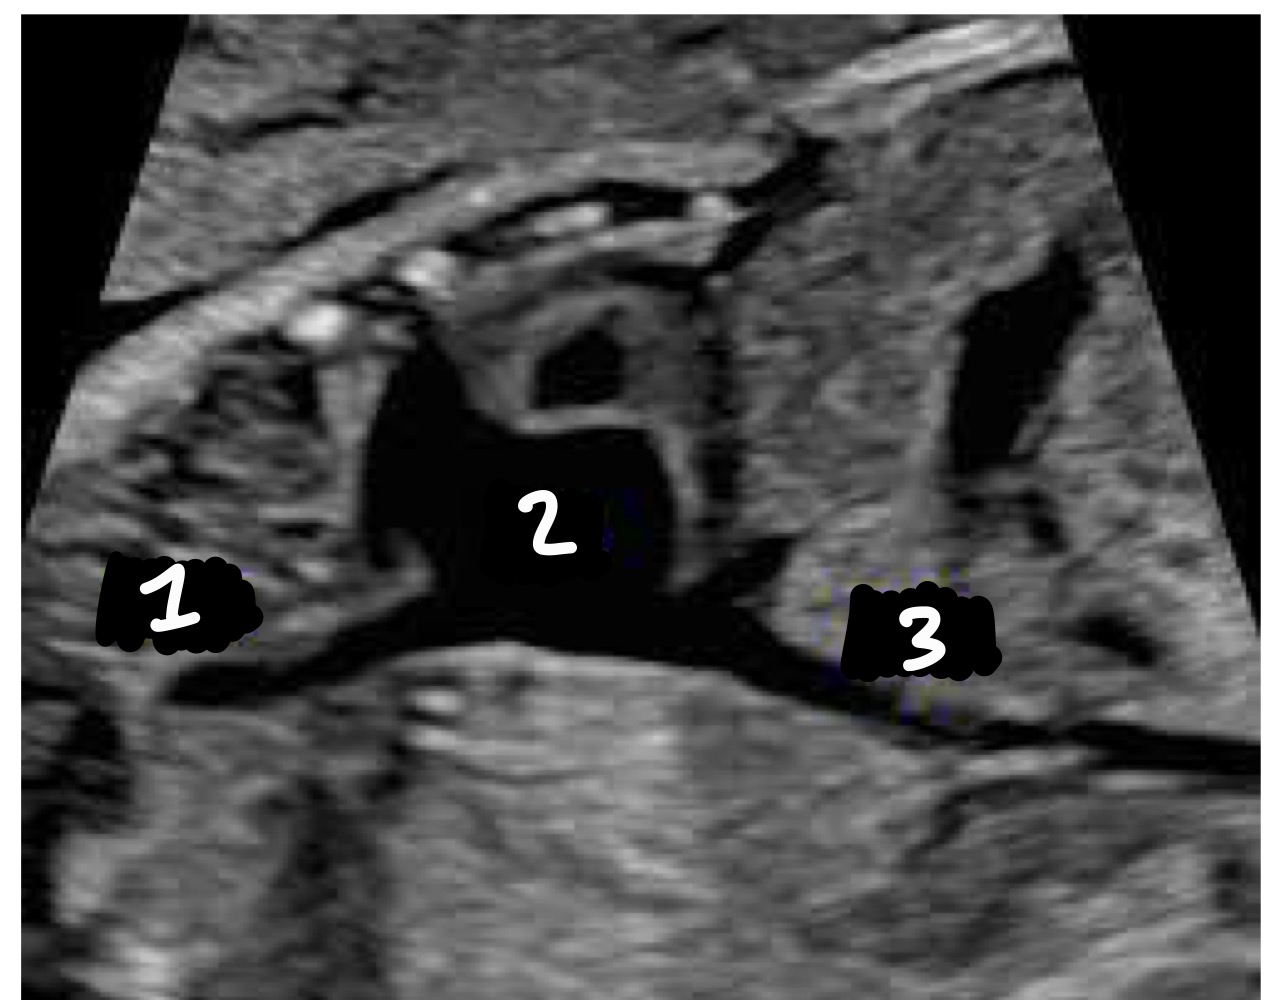

What vessels are seen entering the right atrium in the bicaval view

SVC and IVC

SVC

Right Atrium

IVC

How should the SVC and IVC compare in size

Similar caliber

What does the azygous vein drain

Thoracic and abdominal walls

Aorta

Azygous vein

Where does the azygous vein empty

Into the SVC

Where might the azygous vein be seen

Parallel to the aorta or joining SVC in 3VT